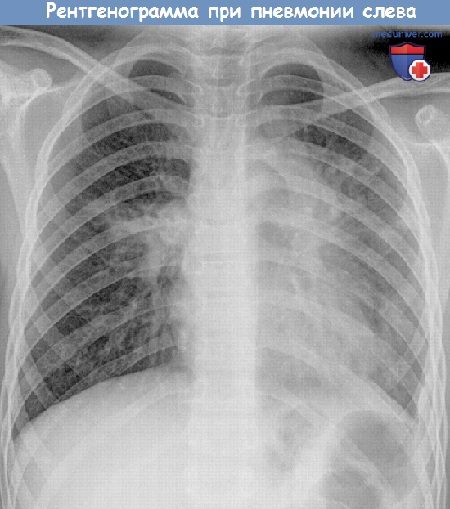

Рентгенография легких

Основным методом исследования, позволяющим поставить точный диагноз при пневмонии, является рентгенография легких. Однако прежде чем отправить человека на такое обследование, терапевт или пульмонолог проводит анализ жалоб пациента и клинический осмотр, включающий применение методов аускультации и перкуссии. Именно данные, полученные при первичном осмотре, позволяют предположить наличие воспалительного процесса в легких и отправить пациента на дальнейшее обследование.

Рентгенограмма при пневмонии у ребенка.

Рентгеновский снимок — обязательный метод исследования при подозрении пневмонии (воспаления легкого).